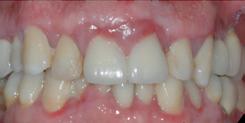

Lorsque le niveau osseux autour de la dent est intact, le recouvrement complet de la récession gingivale peut être obtenu par une intervention chirurgicale.

Le parodontiste choisira entre différentes techniques chirurgicales en fonction du nombre de dents à traiter, de l’importance des récessions et de la qualité de l’environnement tissulaire. Il peut recouvrir la récession soit en déplaçant la gencive environnante, soit en prélevant un greffon (tissu d’environ 1 mm d’épaisseur) au niveau du palais pour recouvrir la récession ou encore en combinant les 2 techniques.